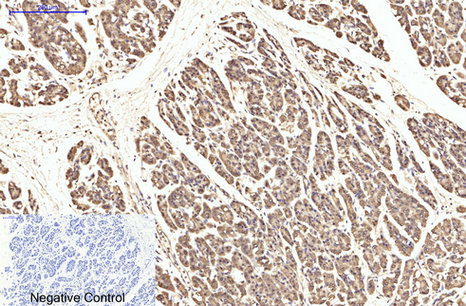

ARG66176 anti-eIF4A1 antibody IHC-P image

Immunohistochemistry: Paraffin-embedded Human colon cancer tissue stained with ARG66176 anti-eIF4A1 antibody at 1:200 dilution (4°C, overnight). Antigen Retrieval: Boil tissue section in Sodium citrate buffer (pH 6.0) for 20 min.

Negative control was used by secondary antibody only.